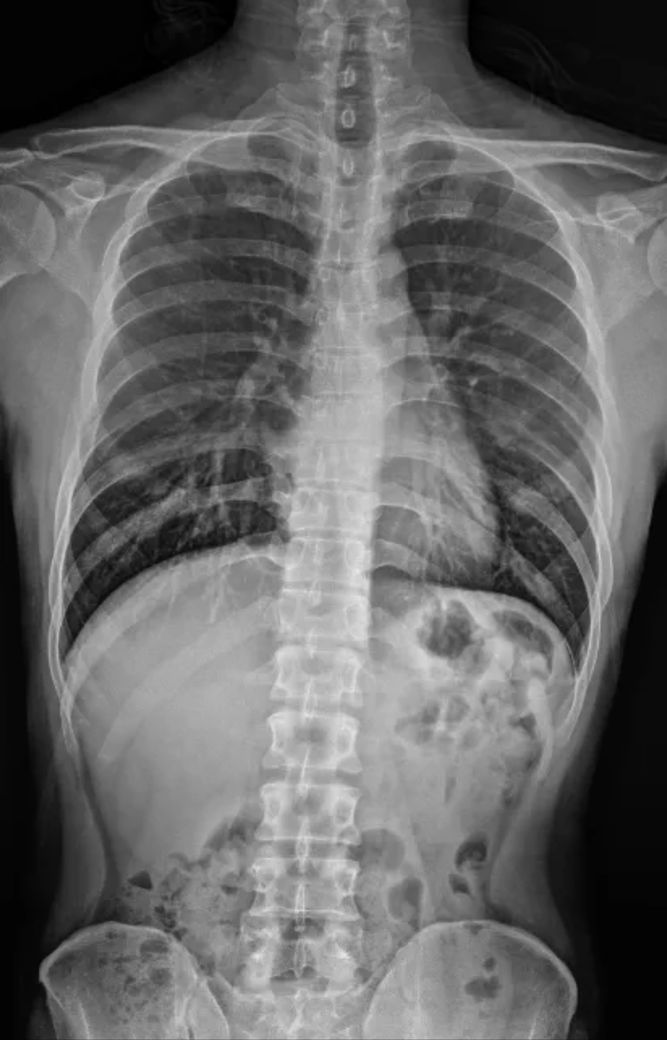

척추가 s자로 휘어진 게 아니고 한쪽으로 기울어져있습니다. 등을 굽혀보면 사람들이 다 척추가 기울어져있다고 말할 정도로 눈에 띄게 기울어져있는데요 아무리 서치를 해도 s자형으로 휘어진 척추측만증에 대한 얘기만 나오고 기울어진 형태는 어떤 치료를 받아야하는지에 대한 정보가 아무것도 없어요ㅠㅠ 저 진짜 이거 치료하고 싶은데 어떻게 해야하나요?

(사진은 서치하다가 저랑 비슷한 고민 하시는 분이 있길래 캡쳐해서 첨부했습니다. 답변어느정도 달리면 수정할 거예요 어쨌든 제 허리는 아닌데 저도 저렇게 기울어져있어요.)

x선 사진을 보시면 머리의 중심부터 한쪽으로 치우쳐져 있으며 몸통의 길이도 한쪽은 길고 한쪽은 짧습니다.

척추 뿐만아니라 전체적으로 신체 중심선을 바로 세우는 운동을 하셔야 할 것 같습니다.